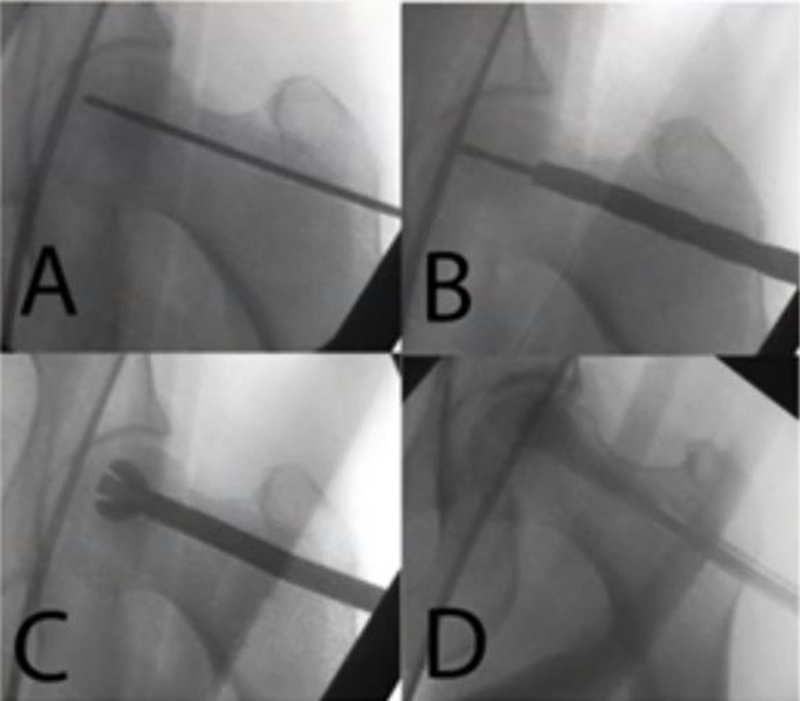

5、髓芯减压联合钽棒植入术

此方法最早由Pedersen提出,直到2005年多孔棒材料才广泛运用到临床研究中,浙江省中医院团队于2009年报告棒植入治疗早期股骨头坏死。一项138髋采取钽棒治疗,平均4年随访时间发现43例(31%)需再次实行髋关节置换术。Tsao在一项长达4年的研究中发现,19个关节(113)进行了再次的THA手术。Floerkemeier报道,在手术平均1.45年后,13例(23)需要再次THA手术,其结论是髓芯减压联合钽棒植入疗效不比单纯髓芯减压好。